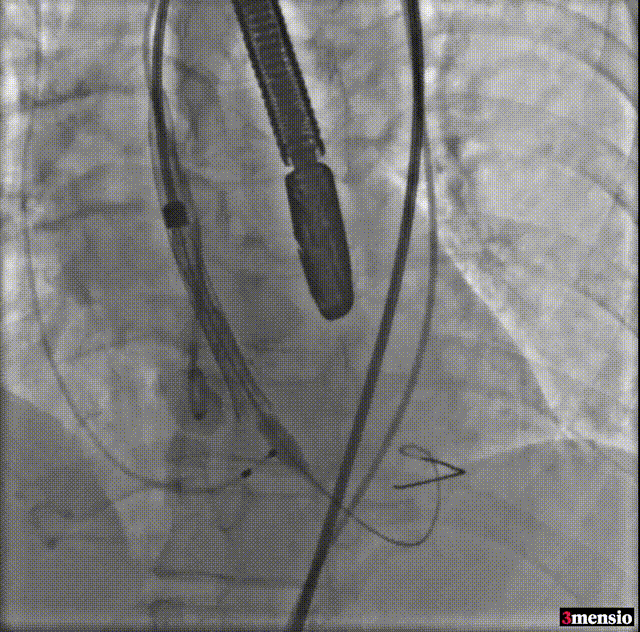

瓣膜释放至工作位

工作位造影

释放后造影